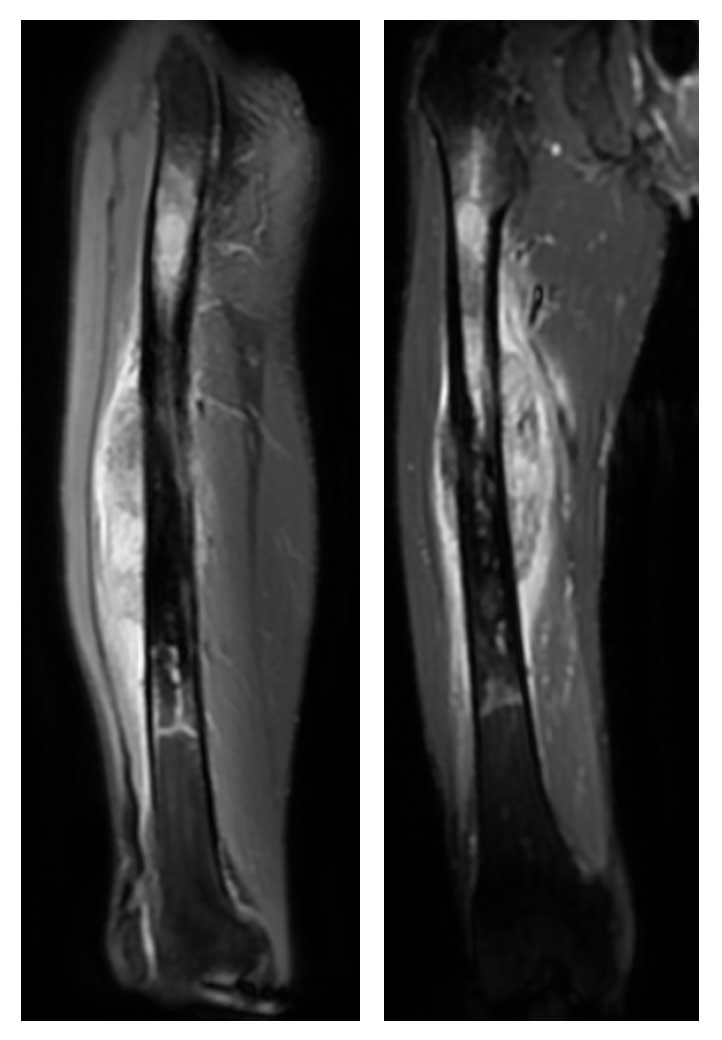

Ameliyat Öncesi: MR’da aynı lokalizasyonda femurun tamamına yakınını dolduran yumuşak dokuya uzanım gösteren ve çevreleyen ödemin eşlik ettiği düzensiz sınırlı tümör dokusu görülmekte.